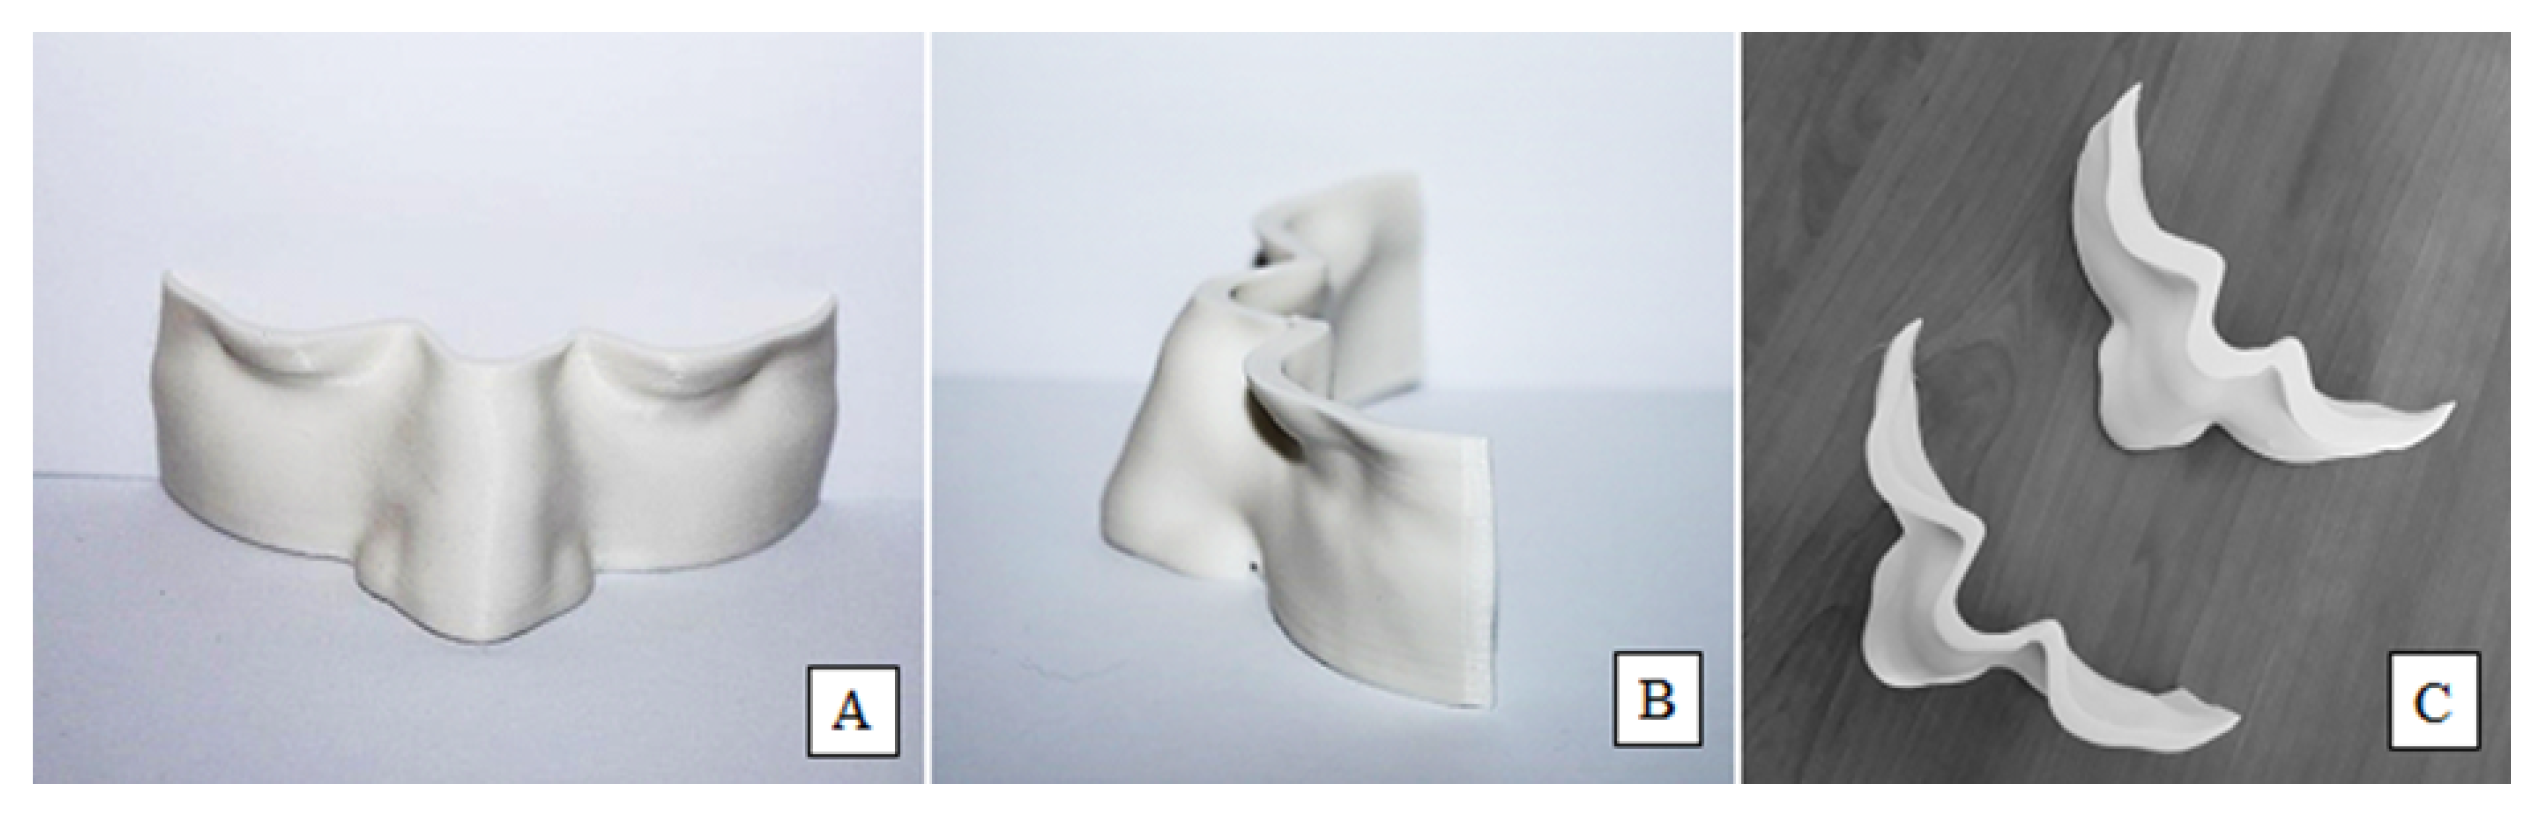

2.1. Development of Personalized 3D Devices

3.2. Conformity of 3D-Printed Bolus